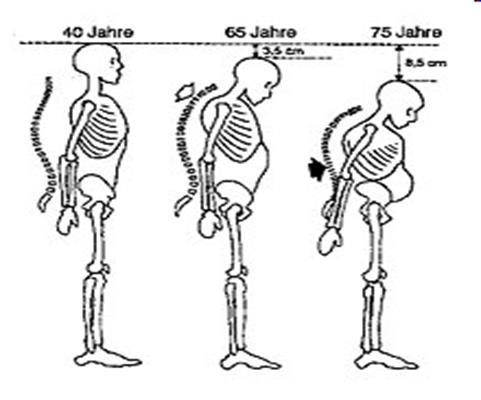

Остеопороз — системне захворювання скелета, яке характеризується зменшенням маси кістки в одиниці об’єму та порушенням мікроархітектури кісткової тканини, що призводить до підвищення крихкості кісток та високого ризику їх переломів.